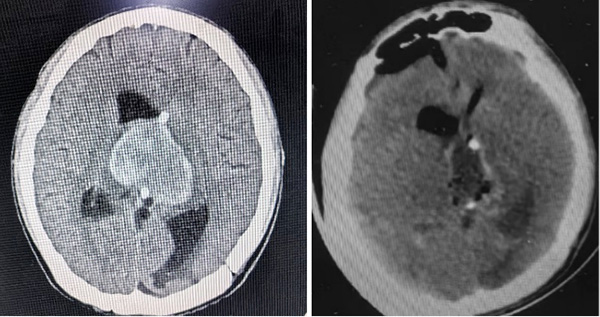

两名患者情况类似,均为颅内巨大肿瘤伴肿瘤卒中,出现因脑干受压,瞳孔增大,如果没有迅速得到处理,患者一般会在几小时内陷入昏迷,造成死亡。面对这种紧急情况,张玉琪教授接到值班医生汇报,没有丝毫犹豫,立即组织团队进行术前准备,并迅速投入到紧张的手术中,张玉琪教授以高超的医术和团队成员、麻醉科的鼎力配合,成功为两名患者完成了急诊手术,最终两名患者均转危为安。

患者2 手术前后脑部CT影像